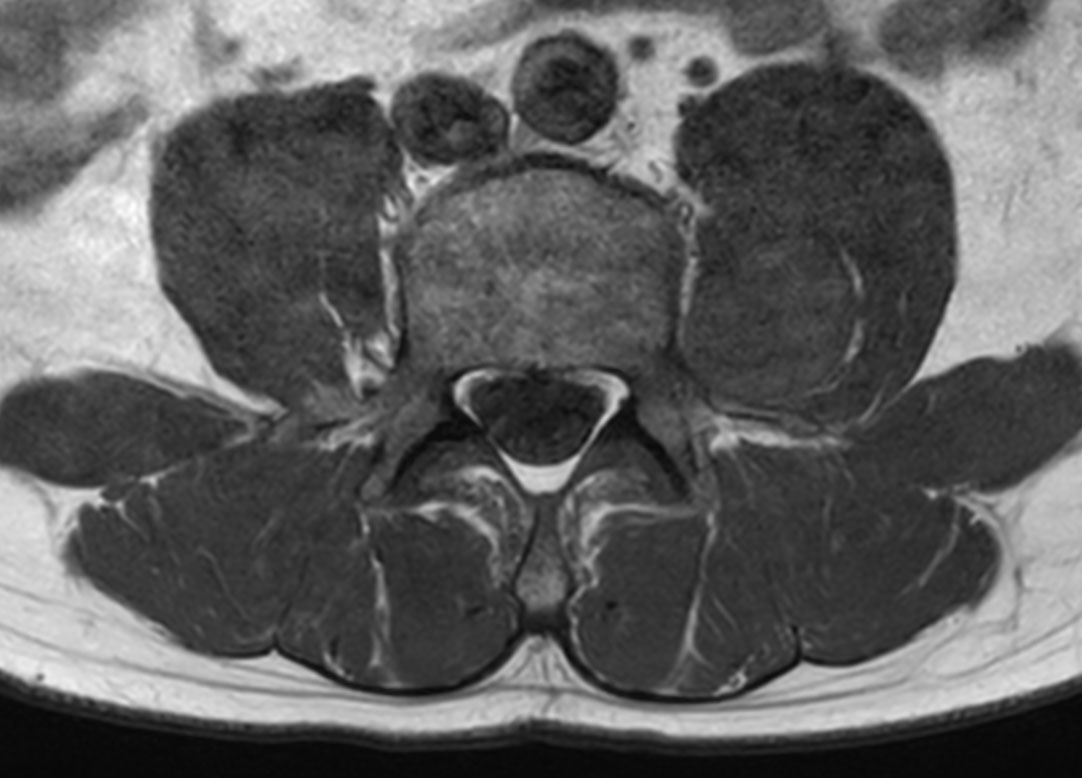

Patient with a lumbar neurography schwannoma.